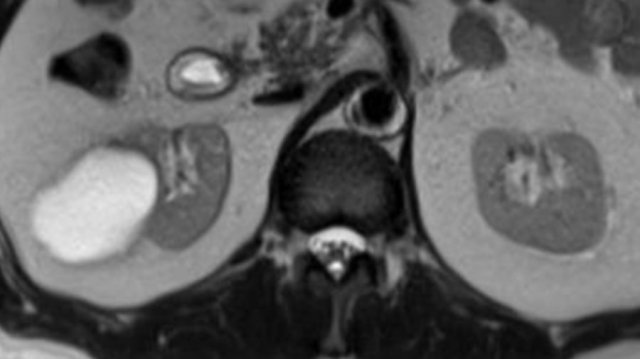

Portovenous scan with an inhomogeneous cystic lesion in the left kidney.

The hyperdense area shows enhancement on the T1W-image with fatsat, in keeping with a solid nodule in a Bosniak 4 cyst.